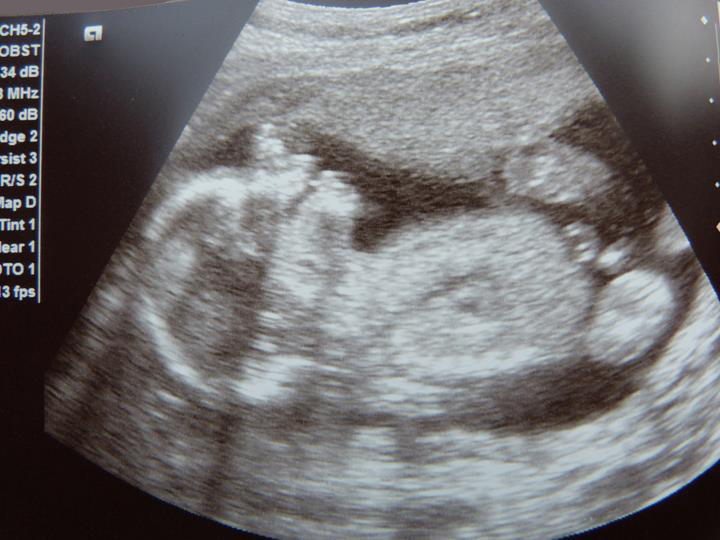

What's The difference Between A 3D And 4D ultrasound?

A look at the differences between 3D and 4D ultrasound images in pregnancy. ... Read Article